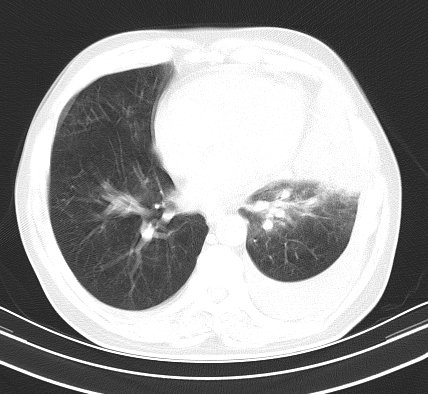

以下是引用老爱克斯新网客在2008-7-31 6:30:00的发言:[br]左肺上叶大片状病灶,左肺上叶支气管狭窄呈鼠尾状,左肺门增大,纵隔内见肿大淋巴结,左侧胸腔积液,余肺清晰。左肺中心型肺癌淋巴结转移,

以下是引用zjb在2008-7-31 6:32:00的发言:[br]左侧中心性肺癌 阻塞性肺炎 肺不张 胸腔积液 建议气管镜

以下是引用zjzjr在2008-7-31 8:45:00的发言:[br]考虑左侧中心性肺癌伴阻塞性肺炎,左肺上叶肺不张,纵隔淋巴结转移;左侧胸腔积液。建议行纤支镜检查。

以下是引用sdzyy在2008-7-31 8:47:00的发言:[br]病灶较治疗前有所进展,胸水增多, 左侧中心性肺癌 并 阻塞性肺炎 肺不张 胸腔积液 可能性大; 建议气管镜检查。 [br] [br]